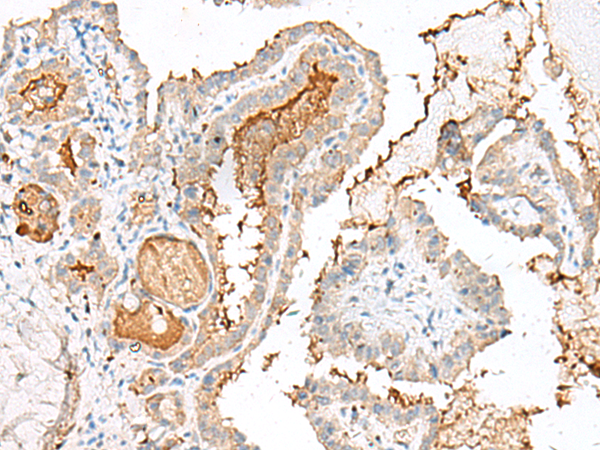

IHC positive control: |

Human colorectal cancer and Human thyroid cancer |

IHC Recommend dilution: |

40-200 |